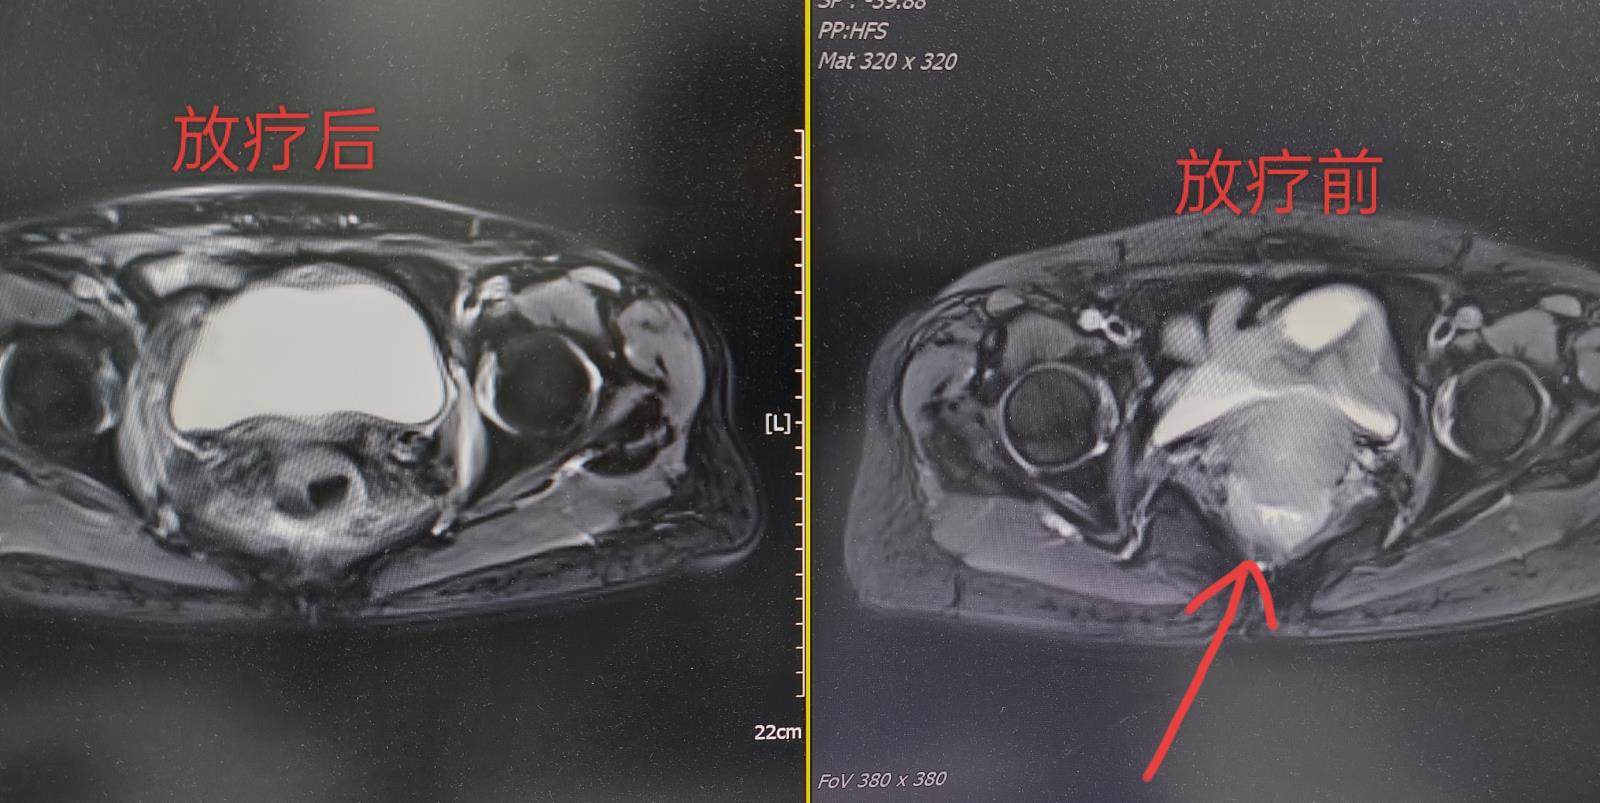

70多岁的王婆婆,1年前于院外行宫颈癌手术,术后病理提示:低分化鳞状细胞癌伴盆腔淋巴结转移,由于各种原因她放弃了选择术后进一步的放射治疗和化学治疗。不幸的是,术后短短半年时间她出现了外阴疼痛不适等症状,复查结果提示:宫颈癌术后复发,肿瘤广泛侵犯直肠、膀胱,此刻的她仍然将化学治疗“拒之门外”,伴随肿瘤复发引起的一系列症状让她生活质量大大下降。

2023年10月,在家人的陪同下抱着将信将疑的态度她来到肿瘤科就诊,经过主治医师对婆婆进行全面评估,并与病人、家属充分沟通各种治疗方案,最终他们选择了在我科进行精准放射治疗以控制肿瘤。方案选择确定后,主管医生按精准放射治疗标准流程为王婆婆及时完成了模拟放疗体位固定、影像学定位,紧接着确定了照射靶区及勾画正常组织与器官,并给出了处方剂量与正常器官限制剂量,由肿瘤科高级医师审核后,物理师按照临床医师的要求利用专业的系统设计射野及布野,物理师与主管医生反复讨论评估,最终为王婆婆确定最优的放疗计划。

2023年10月—2023年12月,王婆婆在家属与肿瘤科医护团队的精心照护下顺利完成了放射治疗,症状得以缓解,生活质量大大改善,病人家属都表示异常感激、选择了相信肿瘤科的医护团队。在最近的复查中提示病灶接近完全缓解,当然,为帮助王婆婆更好的控制、让生活质量再提升,肿瘤科医疗团队也在尽心尽力地与病人、家属沟通全身治疗的方案。